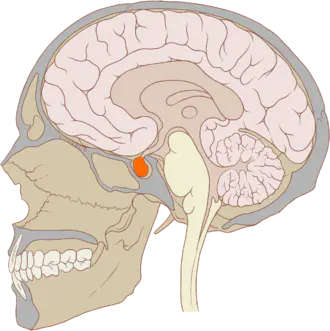

Les craniopharyngiomes sont des tumeurs rares(1) qui se développent à proximité immédiate de l'hypophyse, essentiellement chez l’enfant.

Au cours du développement embryonnaire, l'hypophyse se forme par la fusion de deux structures : l'une en provenance du diencéphale (partie inférieure du cerveau), la seconde - du nom de "poche de Rathke" – en provenance de la cavité orale.

L’hypophyse est une glande très importante, située dans la partie inférieure du crâne. Malgré sa petite taille, elle joue un rôle considérable puisque c’est elle qui sécrète les principales hormones de l’organisme dont l’hormone de croissance.